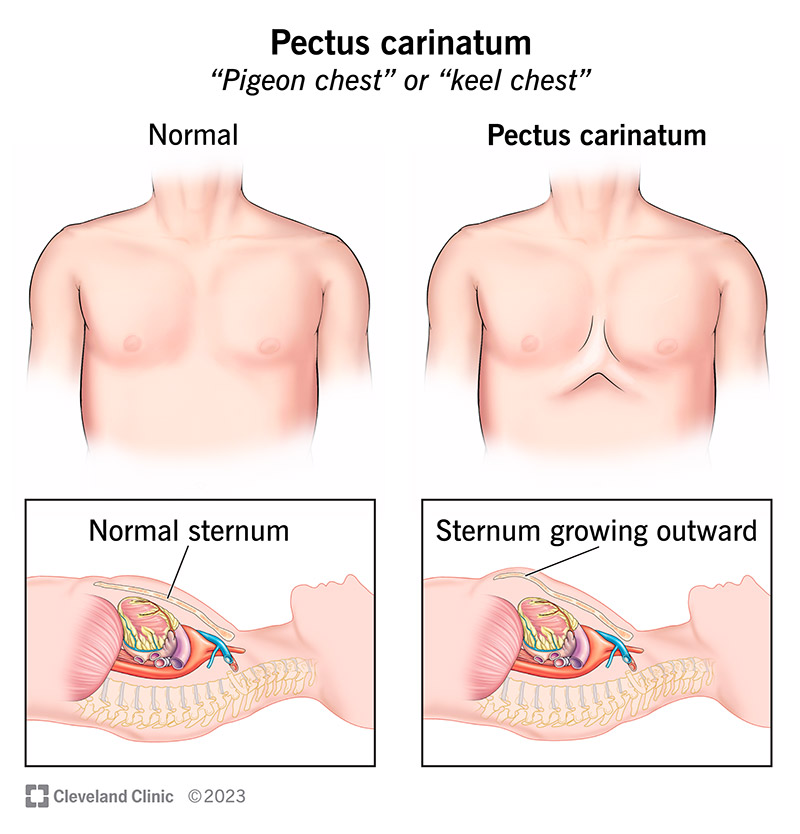

Pigeon chest (પિજન ચેસ્ટ):

- પિજન ચેસ્ટને ‘પેક્ટસ કેરીનેટમ’ (Pectus carinatum) તરીકે પણ ઓળખવામાં આવે છે.

- જેમાં પેક્ટસનો અર્થ ચેસ્ટ થાય છે અને કેરીનેટમ નો અર્થ કીલ ઓફ બોટ થાય છે.

- પેક્ટસ કેરીનેટમ એ ચેસ્ટ વોલની ડીફોર્મિટી છે જેમાં સ્ટરનમ અને રીબ્સ વચ્ચે આવેલ કાર્ટીલેજમાં ઓવર ગ્રોથ જોવા મળે છે જેને કારણે સ્ટરનમ અને રીબ્સ એ આઉટવર્ડ જોવા મળે છે એટલે કે (આગળ નીકળેલા) પ્રોટ્રૂડ થયેલ જોવા મળે છે.

- આથી એન્ટેરિયર પોસ્ટેરીયર ડાયામીટરમાં વધારો જોવા મળે છે.